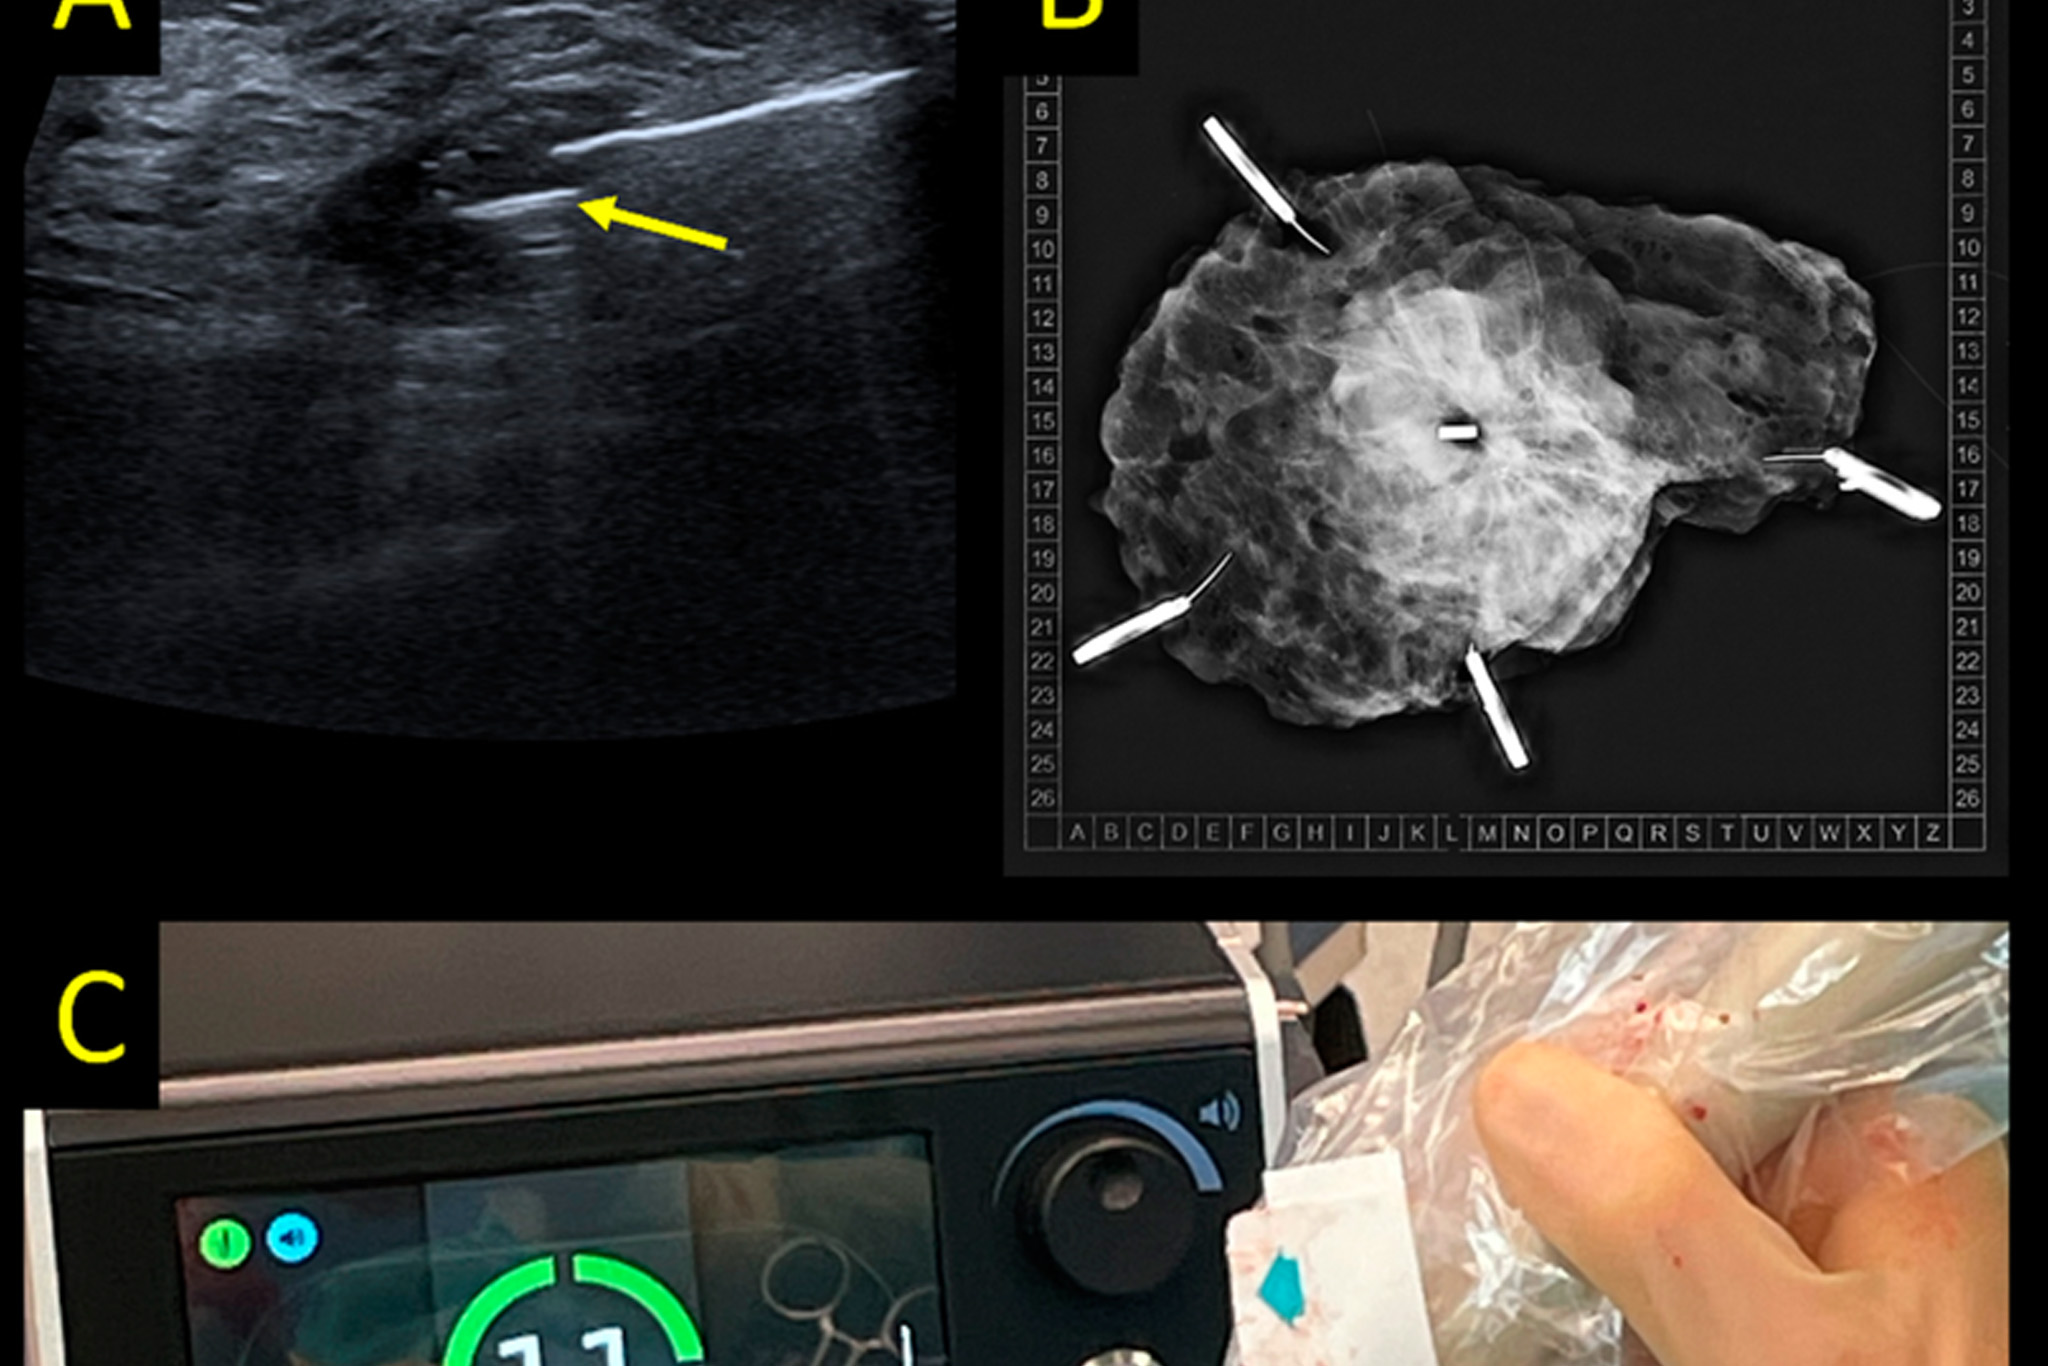

Clip Visibility on Ultrasound

On ultrasound, clip visibility depends on clip design and surrounding tissue. Some clips appear as bright reflective structures with a small acoustic shadow, while others are less conspicuous.

Ultrasound guided localization procedures benefit from clear clip visualization, especially when placing a magnetic seed or wire. For more on biopsy devices that integrate clip placement, read our blog on breast biopsy devices.

From Clip Visibility to Surgical Localization

Before surgery, the clip usually becomes the target for a localization procedure. This can be done using wires, radioactive seeds or non radioactive magnetic seeds. The goal is to transform the static marker seen on imaging into a dynamic guidance tool during the operation.

Magnetic localization systems allow the radiologist to place a seed at or near the clip, and the surgeon to find it with directional guidance in the operating room. For a practical comparison of localization options, see seed localization versus wire guided localization.

How Sirius Medical Supports Clip Based Localization

Sirius Medical focuses on the step after clip placement. The Pintuition Marker® is a non radioactive magnetic seed that can be placed at the clip location before surgery. During the procedure, the Pintuition System® guides the surgeon to the marker through real time visual and audio feedback.